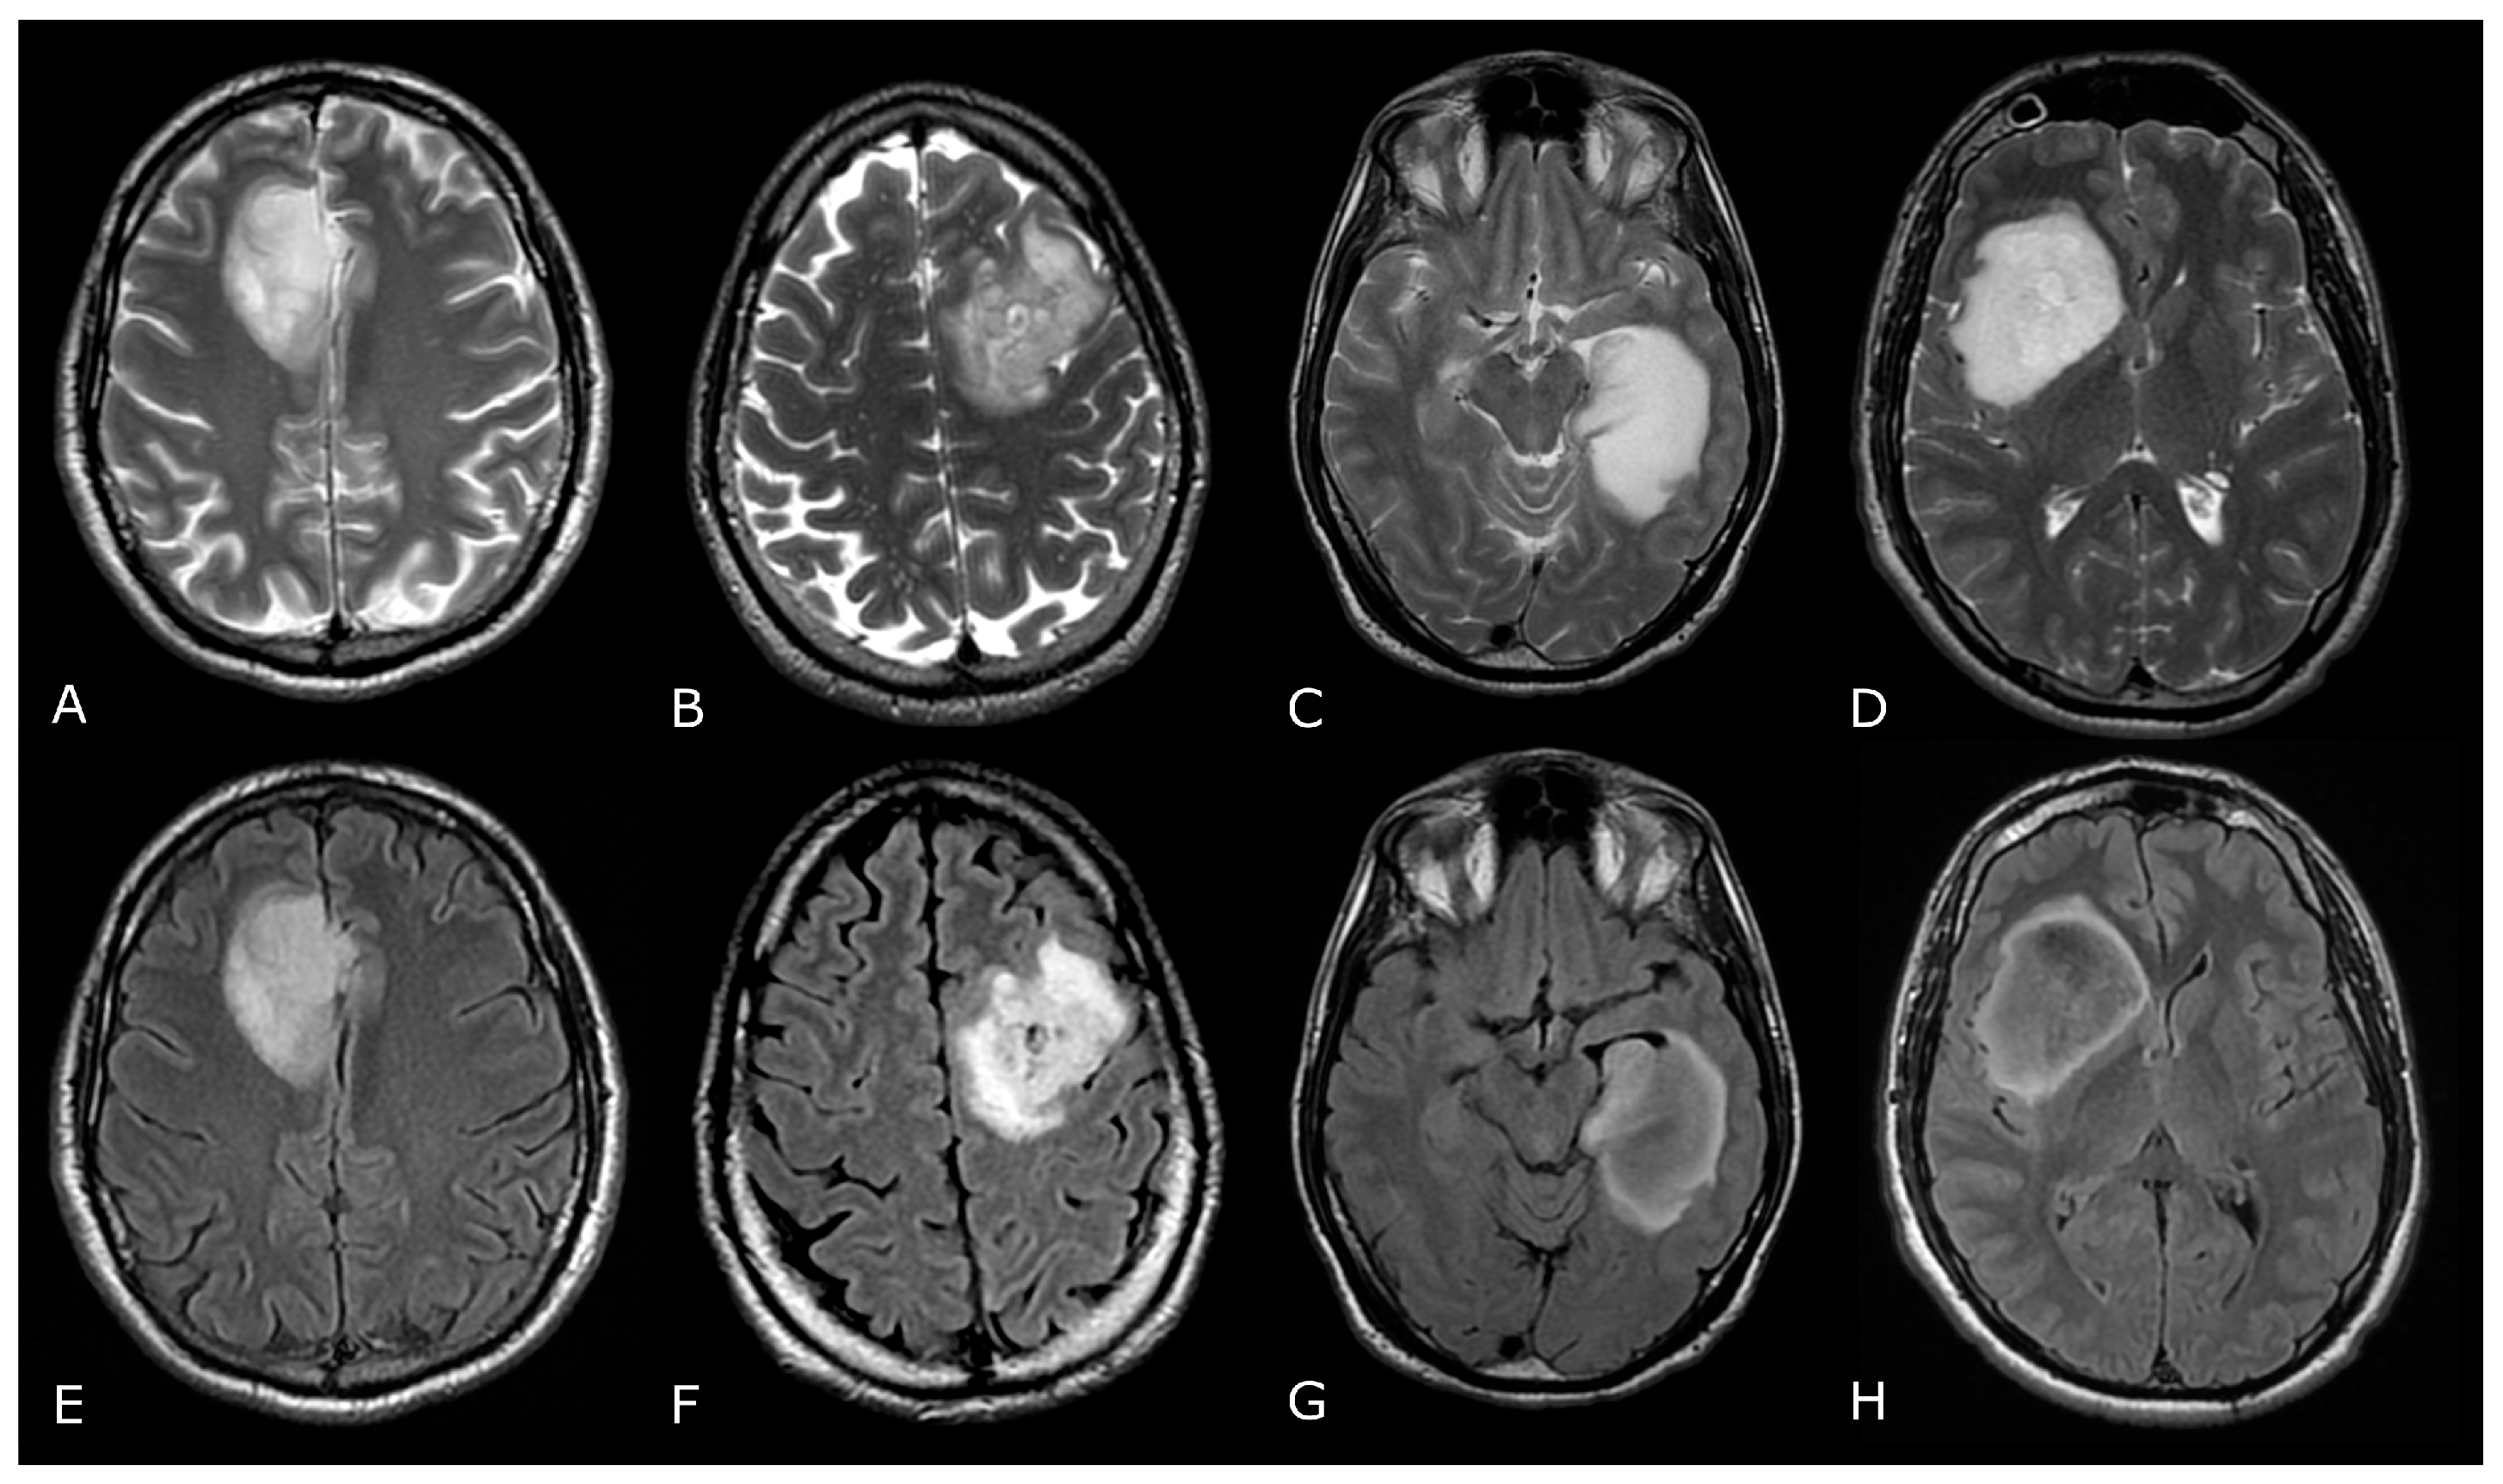

Figure 3.

T2/FLAIR Mismatch Sign. Upper Row Ax T2w images, Lower Row Ax T2-FLAIR images. (A,E); (B,F) IDH-mut, 1p-19q codeleted ODs, respectively grade 2 (A,E) and grade 3 (B,F). (C,G); (D,H) IDH-mut, 1p-19q non codeleted Diffuse Astrocitomas, respectively grade 2 (C,G) and grade 3 (D,H). The T2-FLAIR mismatch sign (C) vs. (G) and (D) vs. (H) represents the T2 signal homogeneity of the mass with relatively hypointense signal throughout most of the lesion on FLAIR except for a peripheral rim of hyperintense signal. Notably, imaging features of grade 3 IDH-mut diffuse astrocytoma and OD may be indistinguishable from grade 2 IDH-mut diffuse astrocytoma and OD. However, grade 3 astrocytoma and OD may have more T2 signal heterogeneity (B,D).